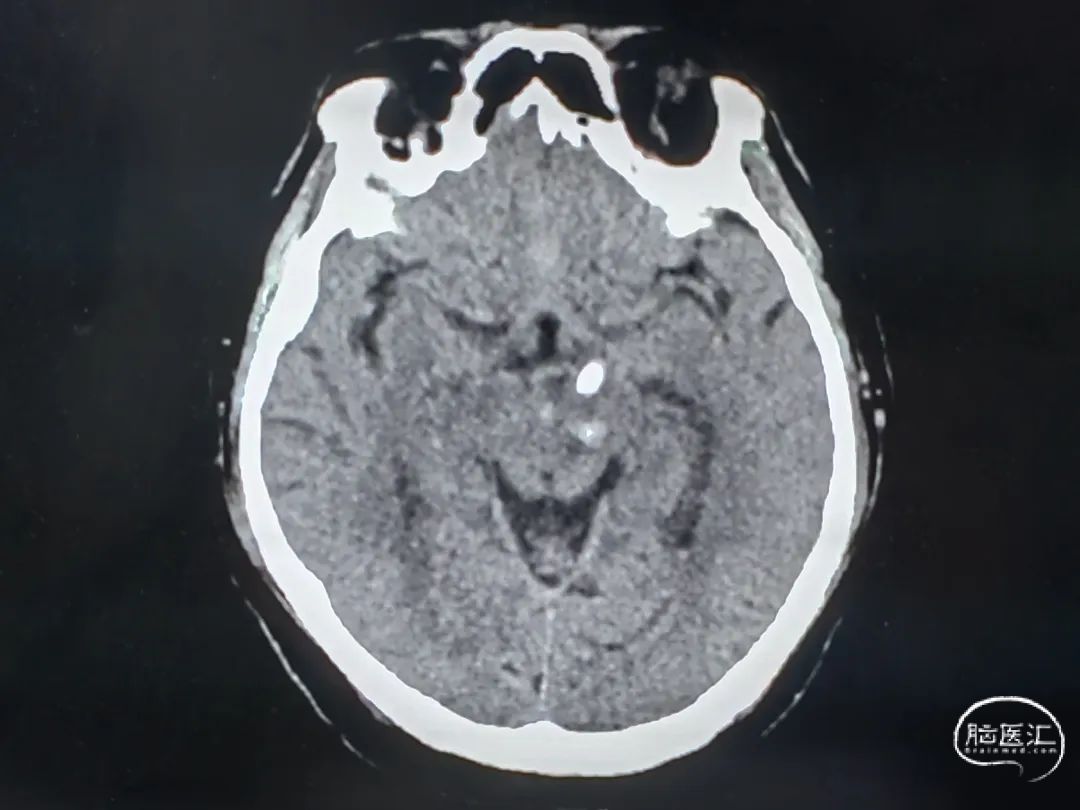

CT扫描后测算脑干血肿穿刺靶点及路径

引流管穿经中脑血肿

引流管准确到达靶点

术后尿激酶应用,术后3天复查CT,血肿引流满意